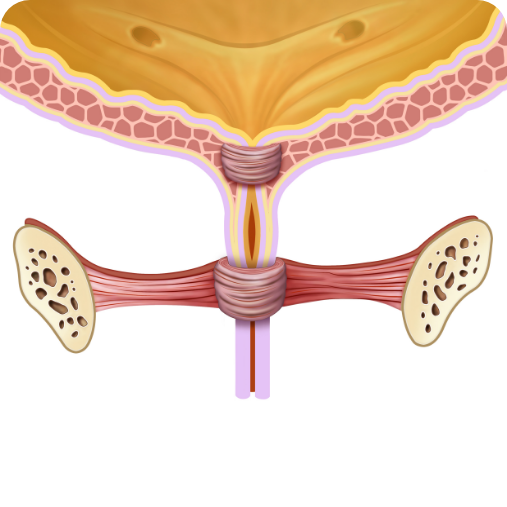

PRIMA del trattamento:

Muscoli deboli dell'uretra

DOPO il trattamento:

Muscoli forti dell'uretra